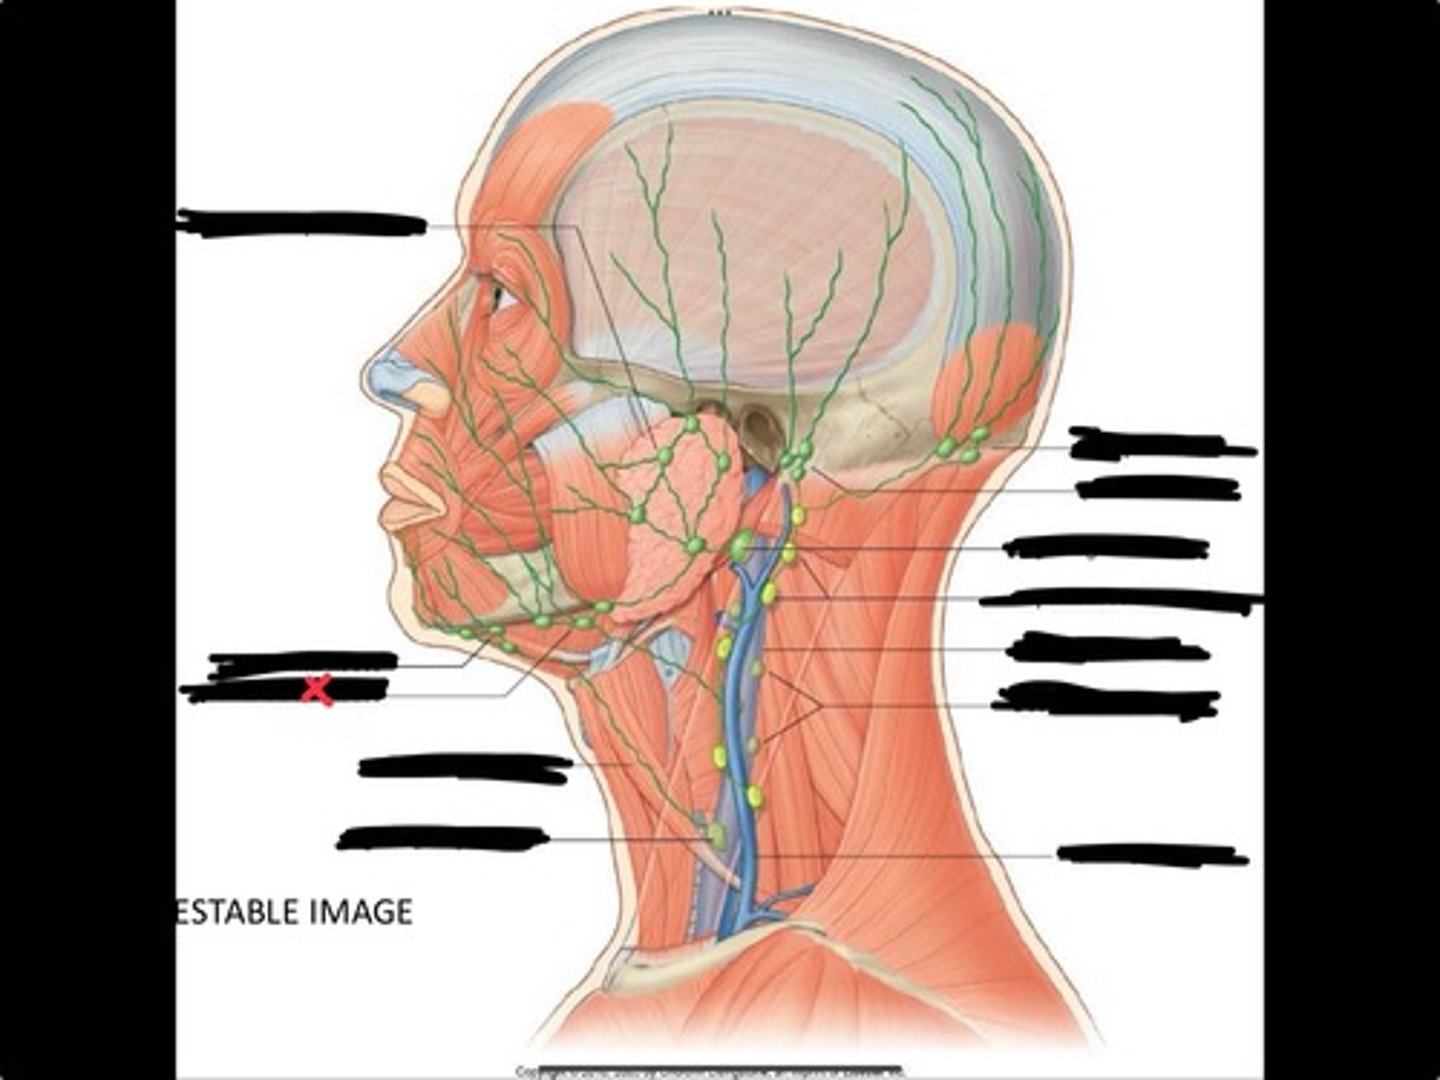

Jugulo-omohyoid node

Omohyoid muscle

Submandibular nodes

Submental nodes

Pre-articular/parotid nodes

Occipital nodes

Mastoid nodes

Jugulodigastric nodes

Superficial cervical nodes

Internal jugular vein

Deep cervical nodes

External jugular vein